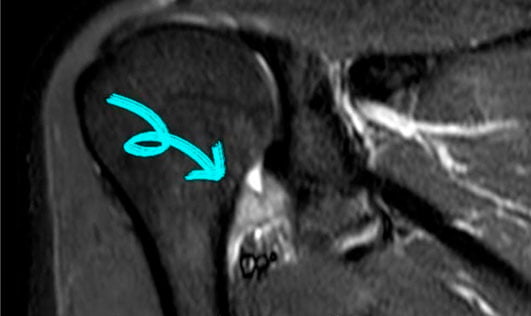

Manguito Rotador

El manguito de los rotadores es un grupo de músculos y tendones que van pegados a los huesos de la articulación del hombro entre ellos están unidos formando un manto sobre la cabeza del húmero, permitiendo que esta se mueva y manteniéndolo estable la articulación. Un desgarro en el manguito de los rotadores ocurre cuando uno de los tendones se desprende del hueso. El más común en desprenderse es el tendón supraespinoso.

Desgarros

Los desgarros del manguito de los rotadores pueden ocurrir de dos maneras:

- Un desgarro repentino o agudo puede suceder cuando usted se cae sobre su brazo mientras está estirado. También puede suceder después de un movimiento súbito de un tirón al tratar de levantar algo pesado.

- Un desgarro crónico del tendón del manguito de los rotadores ocurre lentamente con el tiempo. Es más probable cuando usted tiene tendinitis crónica o síndrome de pinzamiento. En algún momento, el tendón se desgasta y se rompe.

En las roturas parciales habitualmente pequeñas (menores a 6mm) usamos mismo tratamiento, pero roturas más grandes o complejas en pacientes activos sugerimos la reparación ya que las roturas de tendones no tienen potencial de cicatrización espontánea y el tratamiento paliativo suele ser de pobre respuesta.

El tratamiento quirúrgico suele ser una eficaz técnica para alivio del dolor o su desaparición. Existen técnicas abiertas y artroscópicas. La técnica artroscópica es la preferida por nosotros ya que evita seccionar el músculo deltoides.

Durante la cirugía se utilizan unos implantes llamados arpones para fijar el tendón que es un tejido blando en el hueso que es un tejido duro. El arpón consta de dos partes una parte que va dentro del huello que es como un tornillo de plástico, y lleva unas suturas en su interior de alta resistencia que sirve para fijar el tendón.